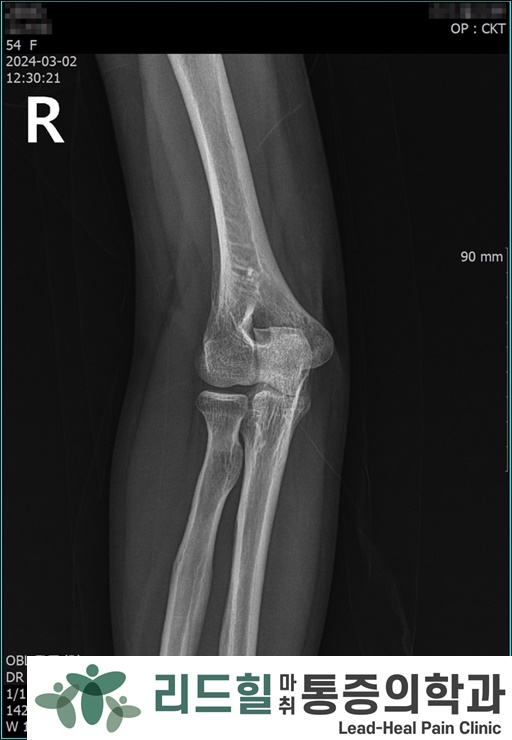

X-ray 검사 결과 : 석회화나 골극, 관절증 등의 이상 소견 없음